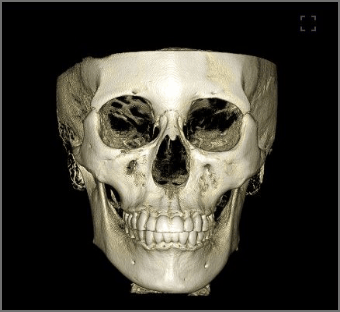

- 前額から顎下まで、歪の無い画像取得。FOV180×160

前額から顎下まで、歪の無い画像取得。FOV180×160

発展するデジタル広域解析に対応した撮影領域。

3D矯正解析、3D口腔内模型、3D顔貌それぞれのデータを融合した総合解析に対応するこれからのCTモデル。 精巧なそれぞれのデジタル診療情報を包括的に解析するための次世代診療に適した広域CT情報を提供します。

非合成の360度フルスキャン

データ合成無く、1回で360度フルスキャン N点(眉間)からGn点(顎)まで、わずか16秒でスキャン、広範囲を迅速かつ正確に診断します。